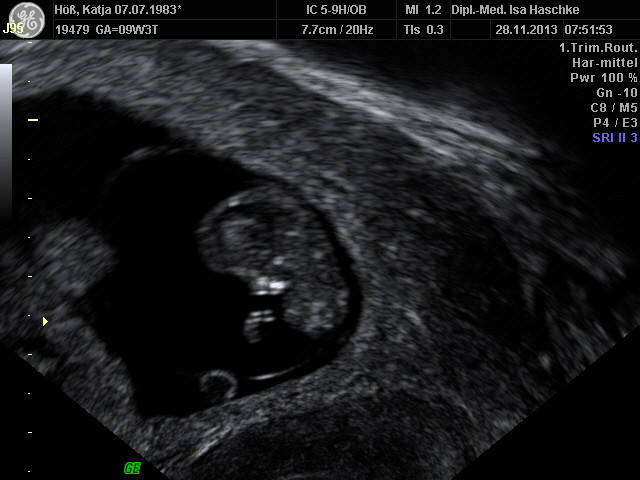

Schwangerschaftswoche 10

Besonderer Heißhunger:  nur auf Döner und zum trinken Tee

Beschwerden:                 keine Morgenübelkeit; nur leichte Krämpfe

in der Leistengegend

Bauchumfang:                90 cm

Brustumfang:                 96 cm